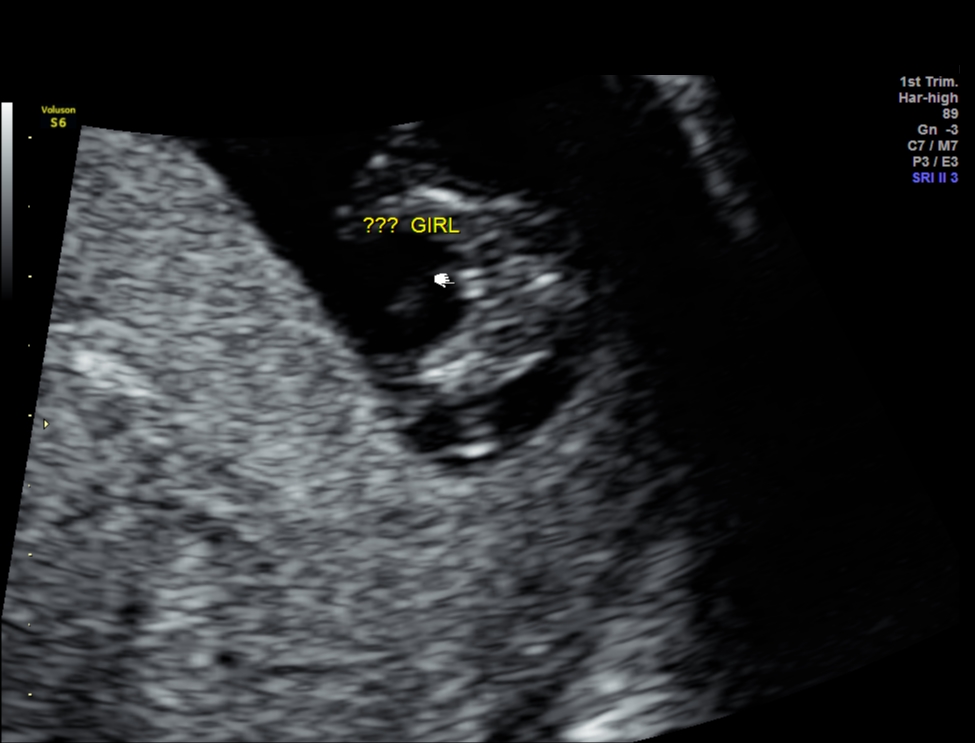

Attachment 33525

HI everyone, This is my 1st post in this forum after reading many threads about gender predictions and some of you ladies are very knowledgable. These are my NT scan pics for today.

One picture I asked tech what the gender is and she said she was very unsure but it might develop to girl part. What do you guys think? I googled some boys potty shot also has three lines and why mine is protruding ???